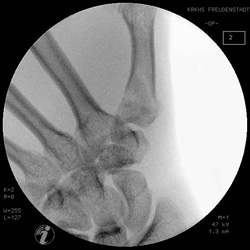

Die Frakturkontrolle muß in allen Ebenen kontrolliert

werden.

Mit einem Kirschnerdraht wird vorgebohrt und danach

die Schrauben plaziert. Zwei Schrauben in das Trapezium und zwei Schrauben

diestal der Fraktur.